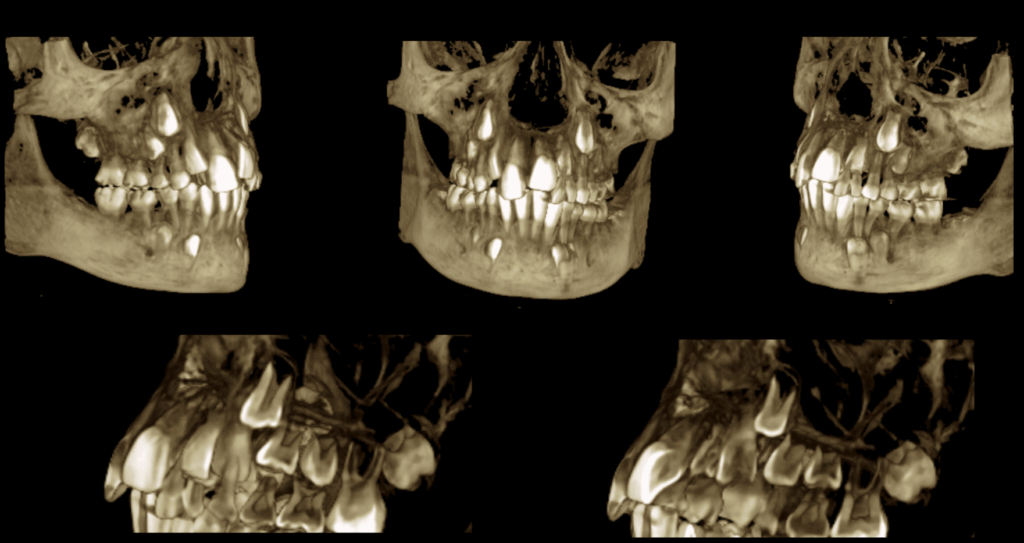

En la reconstrucción 3D se representa las características y ubicación de pieza supernumeraria y pieza 22 (Figura 4).

RECONSTRUCCIÓN 3D